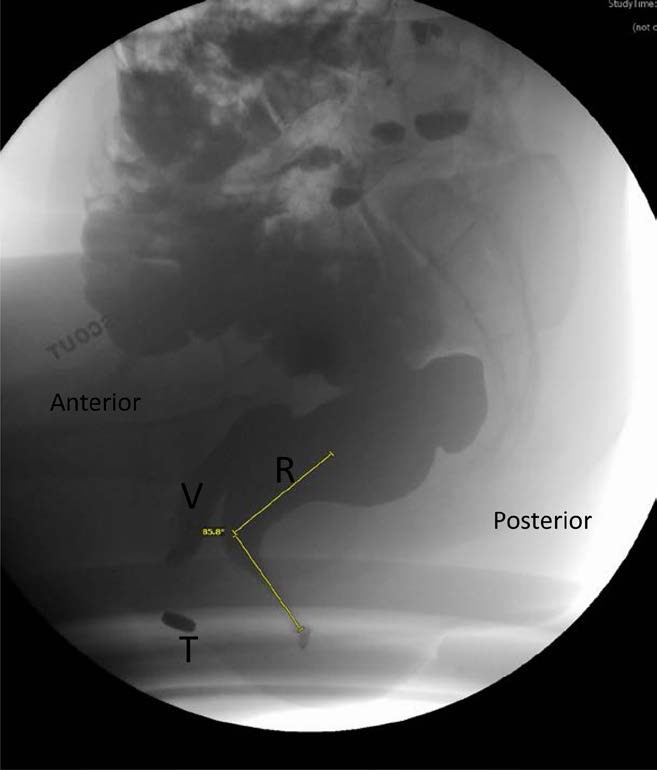

The anorectal angle is the angle between a line parallel to the posterior wall of the ampullary portion of the rectum and a line drawn along the anal canal (Fig. 7, Video 2) . This angle is observed during Kegel and at peak straining during defecography and compared to the angle at rest. The angle should become more acute during Kegel. In healthy individuals, the resting angle is approximately 85 to 96 degrees, which decreases by 10 to 15 degrees during Kegel and becomes more obtuse during straining in comparison to the angle at rest[41],[42] (Fig. 8). However, due to poor reproducibility, many radiologists do not measure the actual degree of change in the anorectal angle, and instead comment on whether the angle widens, narrows, or stays the same.[43]